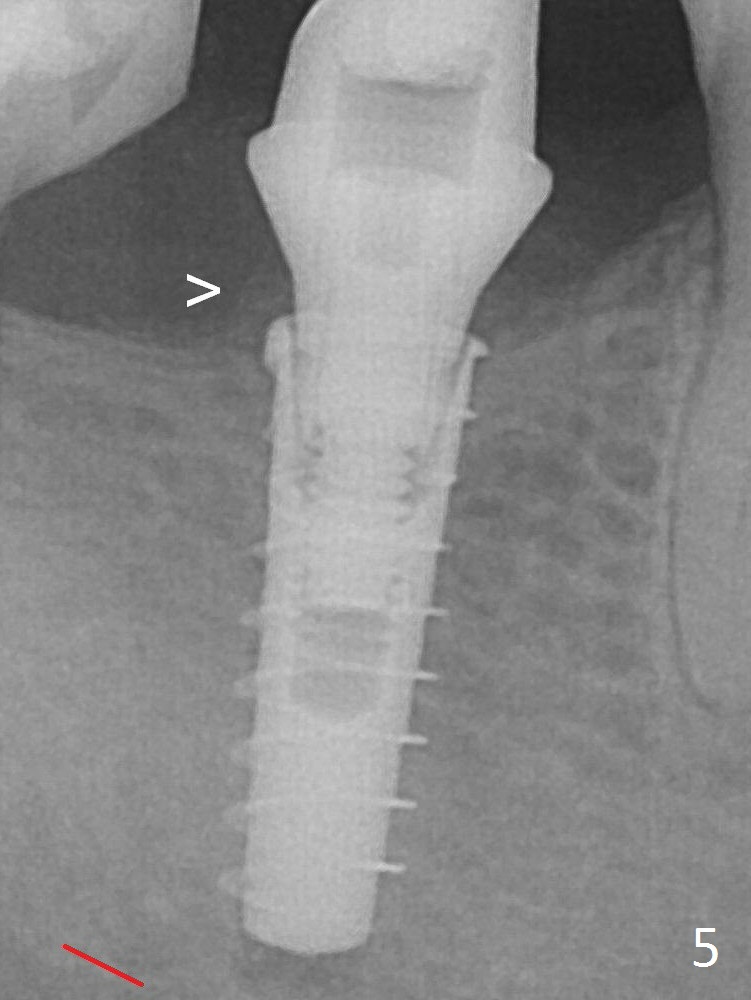

After increasing the osteotomy 1-2 mm, the implant is placed deeper; the autogenous bone with Osteogen is placed around the plateau of the implant (Fig.5 >), particularly buccally, followed by collagen membrane.